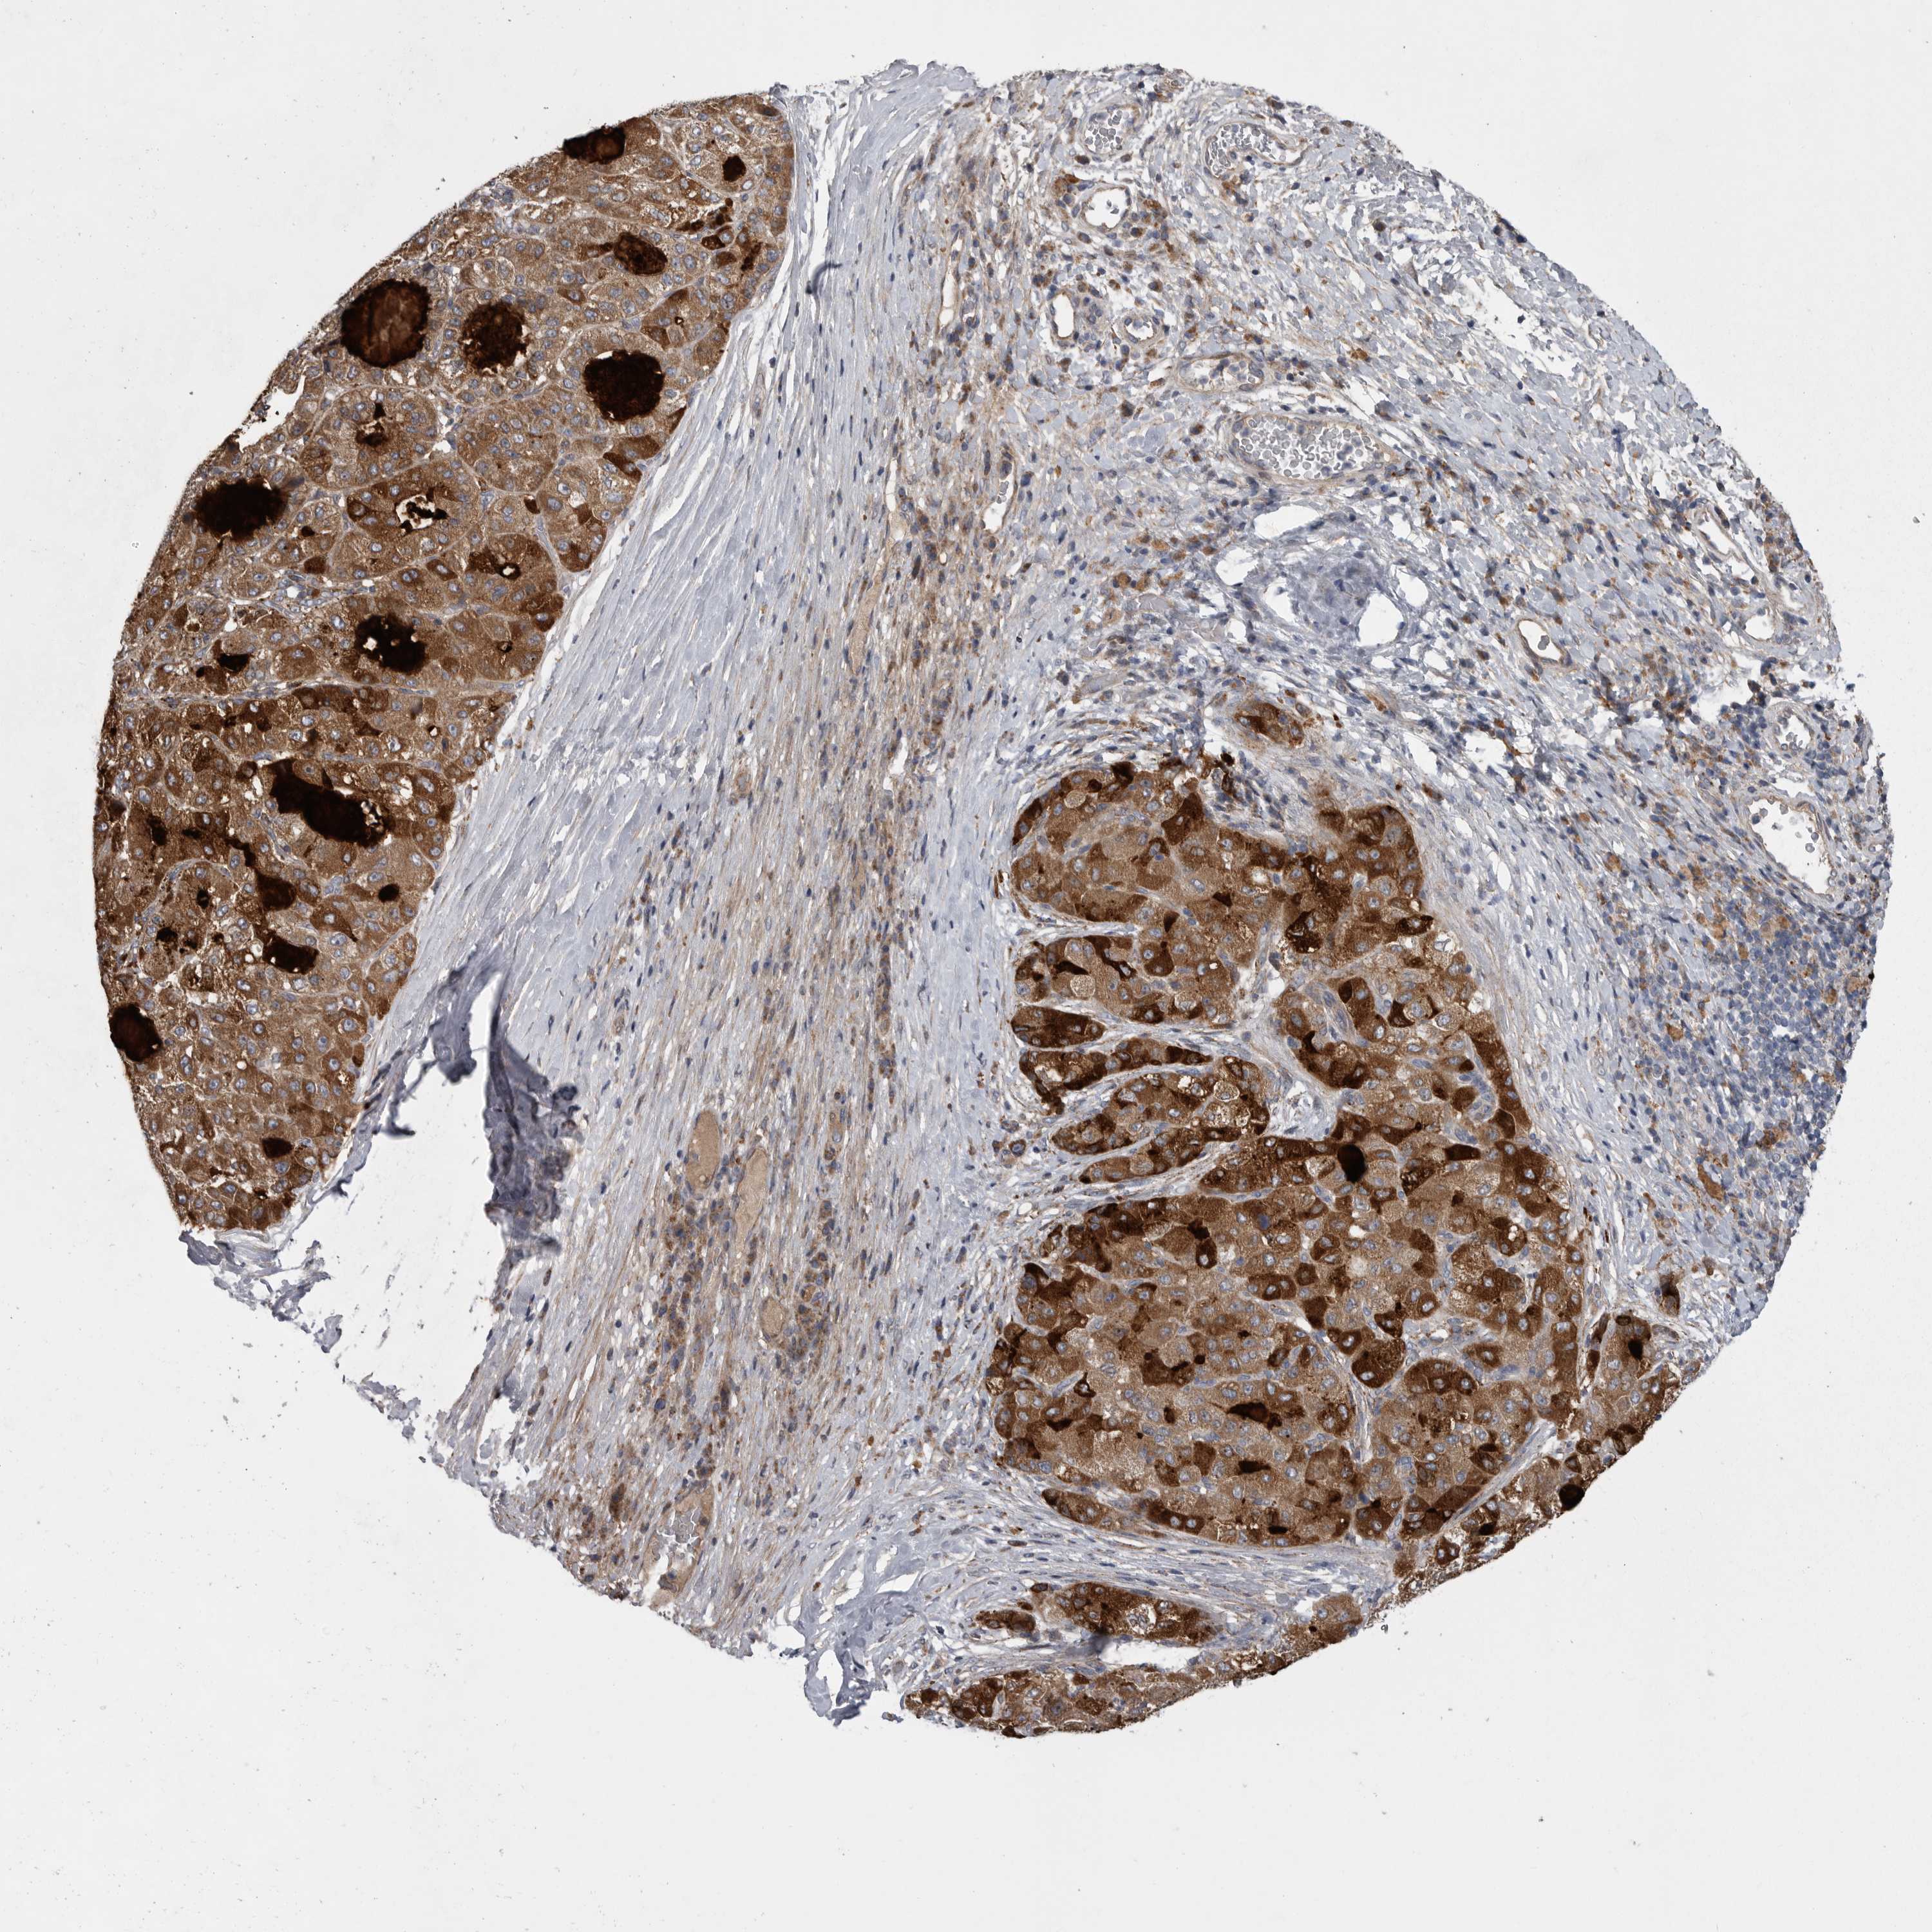

LIVER CANCER - Protein expressioni

A mouse-over function shows sample information and annotation data. Click on an image to view it in a full screen mode. Samples can be filtered based on level of antibody staining by selecting one or several of the following categories: high, medium, low and not detected. The assay and annotation is described here.

Note that samples used for immunohistochemistry by the Human Protein Atlas do not correspond to samples in the TCGA dataset.

Antibody stainingi

Antibody staining in the annotated cell types in the current human tissue is reported as not detected, low, medium, or high, based on conventional immunohistochemistry profiling in selected tissues. This score is based on the combination of the staining intensity and fraction of stained cells.

Each image is clickable and will lead to virtual microscopy that enables deeper exploration of all samples and also displays staining intensity scores, fraction scores and subcellular localization as well as patient and tissue information for each sample.

Antibody HPA027367

Antibody HPA027396

Antibody CAB005036

Staining

High

Medium

Low

Not detected

Intensity

Strong

Moderate

Weak

Negative

Quantity

>75%

75%-25%

<25%

None

Location

Nuclear

Cytoplasmic/membranous

Cytoplasmic/membranous,nuclear

Cholangiocarcinoma

Carcinoma, Hepatocellular, NOS